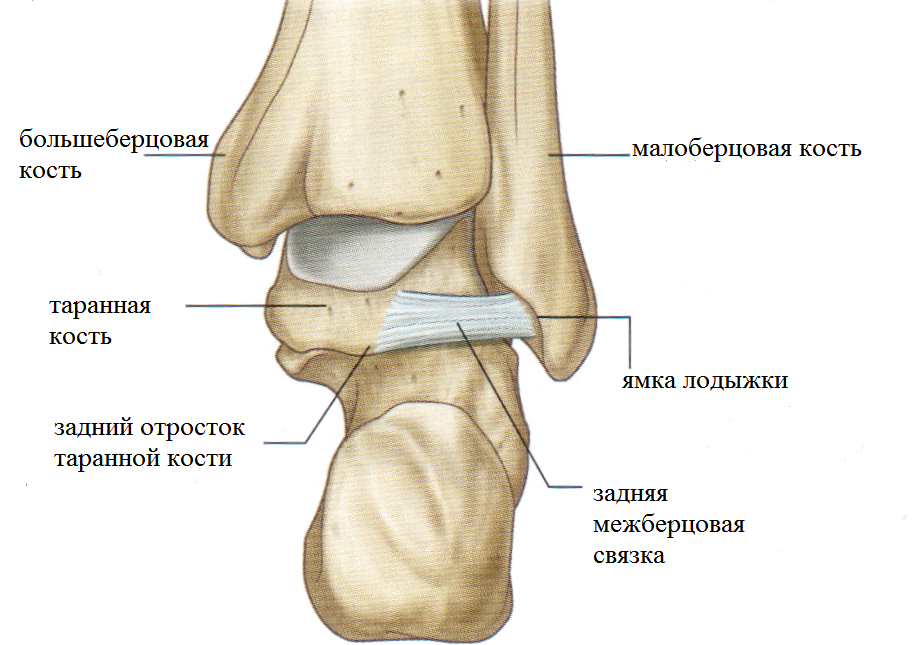

Анатомия суставов Шапарова и Лисфранка: фото и информация